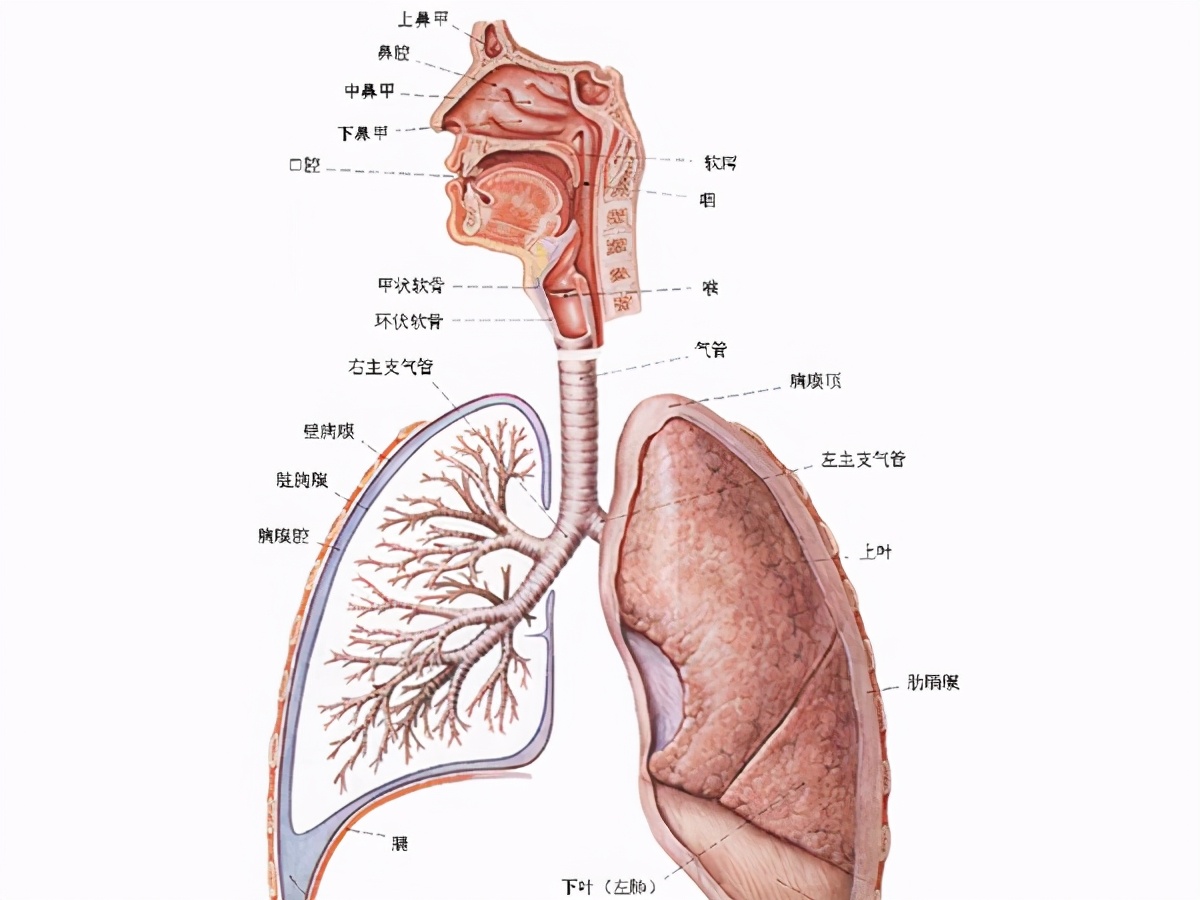

所有分类 初中教育 理化生 发生在肺里的气体交换动画ppt 一,肺的位置

发生在肺内的气体交换,第三章人体的呼吸,,肺的位置,,,位于胸腔内

人教版生物七年级下册432发生在肺内的气体交换课件共24张ppt